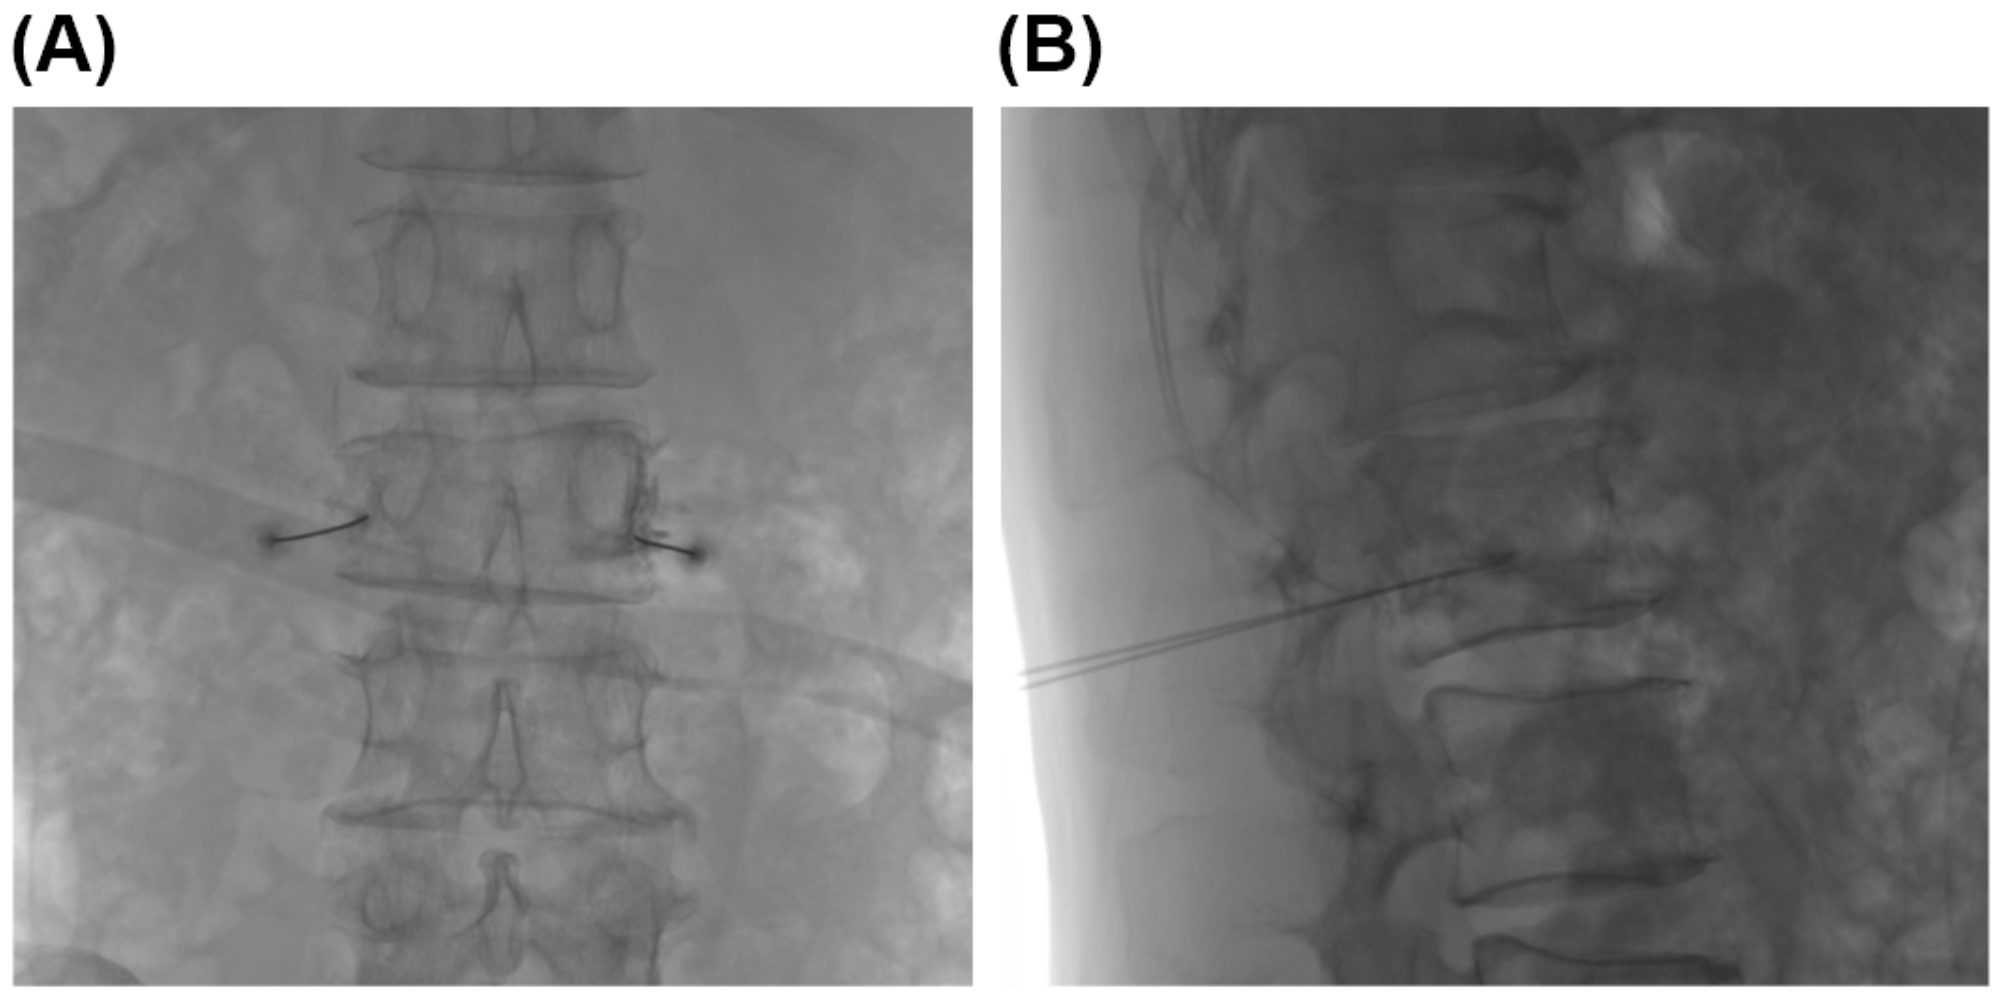

2.2. Gray Ramus Nerve Block